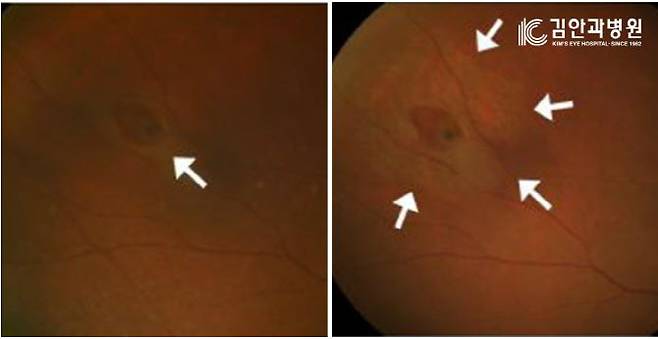

망막박리는 원인에 따라 열공성, 견인성, 삼출성 망막박리 3가지로 분류할 수 있다. 열공성 망막박리는 가장 흔하게 발견되는 형태로, 망막전층의 구멍(열공)으로 인해 신경상피가 망막색소상피와 분리되고 그 사이에 액체가 차게 되어 발생한다. 대표적인 원인으로 유리체가 떨어지는 현상인 후유리체박리가 있으며, 그 외에 고도근시, 안내수술, 안구 좌상, 천공상, 안내염증, 맥락망막결손 등으로 발병할 수 있다.

망막박리는 안과에서 응급질환으로 간주하기 때문에 초기에 발견하는 것이 중요하다. 대부분의 경우 수술로 치료하는데, 눈 바깥에서 접근해 시행하는 공막돌륭술과 공막두루기술 그리고 눈 안으로 접근해 시행하는 유리체절제술이 있다. 비수술 치료 방법인 기체망막유착술은 안구 내로 기체를 주입하는 시술법으로 지금은 거의 시행하지 않고 있다.